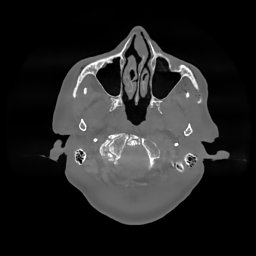

The results for simulated noisy data are shown in Fig. 2. The first and third rows display two representative slices from the test set, and the second and fourth rows present the corresponding error maps. The traditional WCE method suppresses cupping artifacts and recovers some missing anatomical structures but still shows noticeable deviations from the ground truth. Predictions from the four diffusion-based models demonstrate a markedly improved ability to restore anatomical structures. Among them, cDDPM fails to fully reconstruct the patient bed and retains residual noise in its outputs. This noise is attributable to an incomplete reverse denoising process rather than residual Poisson noise, as evidenced in our noise-free experiments (Fig. 5 in the Appendix). PatchDiffusion, diffusionGAN, and I2SB achieve similar visual quality, with I2SB producing the cleanest and most consistent reconstructions.

Quantitative results in Tab. V further confirm I2SB’s superiority over conventional deep learning methods such as FBPConvNet and Pix2pixGAN across RMSE, PSNR, and SSIM. Compared to other diffusion models—including cDDPM, PatchDiffusion, and cLDM—I2SB delivers higher image quality, while diffusionGAN achieves comparable quantitative performance. However, I2SB demonstrates a significant advantage in inference efficiency, as summarized in Tab. IV.

III-D Real Clinical Data Experiment

The experimental results on clinical head data are shown in Fig. 4. The reference images were reconstructed using the fast iterative shrinkage-thresholding algorithm (FISTA) with total variation regularization from non-truncated projection data. In the WCE reconstructions (Fig. 4(b)), severe truncation prevents accurate recovery of anatomical structures outside the FOV. Despite being trained solely on simulated data with a domain gap, all deep learning models can restore a substantial portion of the missing anatomy. Among them, the diffusion-based methods recover soft-tissue boundaries more faithfully than the conventional deep learning approach FBPConvNet, highlighting their stronger image generation capability. However, cDDPM reconstructions exhibit more noticeable noise than those from other methods, consistent with the simulated data results. The patchDiffusion model introduces artifacts within the FOV, likely due to its patch-wise processing strategy. While I2SB shares the same limitations as other diffusion models in perfectly restoring soft-tissue detail, it produces fewer residual noise patterns and fewer artifacts within the FOV boundaries. Overall, Fig. 4 demonstrates the strong efficacy of I2SB in reconstructing real CBCT data.